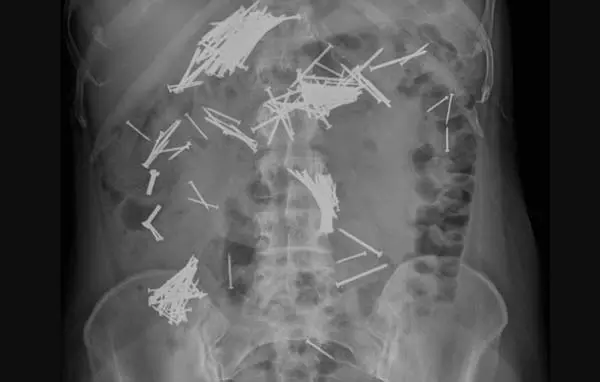

의료진이 복부 엑스레이 검사를 한 결과, 배에 광범위하게 못들이 퍼져 있었다. CT 사진을 통해서도 위, 장 등에 많은 양의 금속 이물질이 발견됐다. 이물질 수가 너무 많아 내시경 시술로 제거할 수 없는 상태였다.